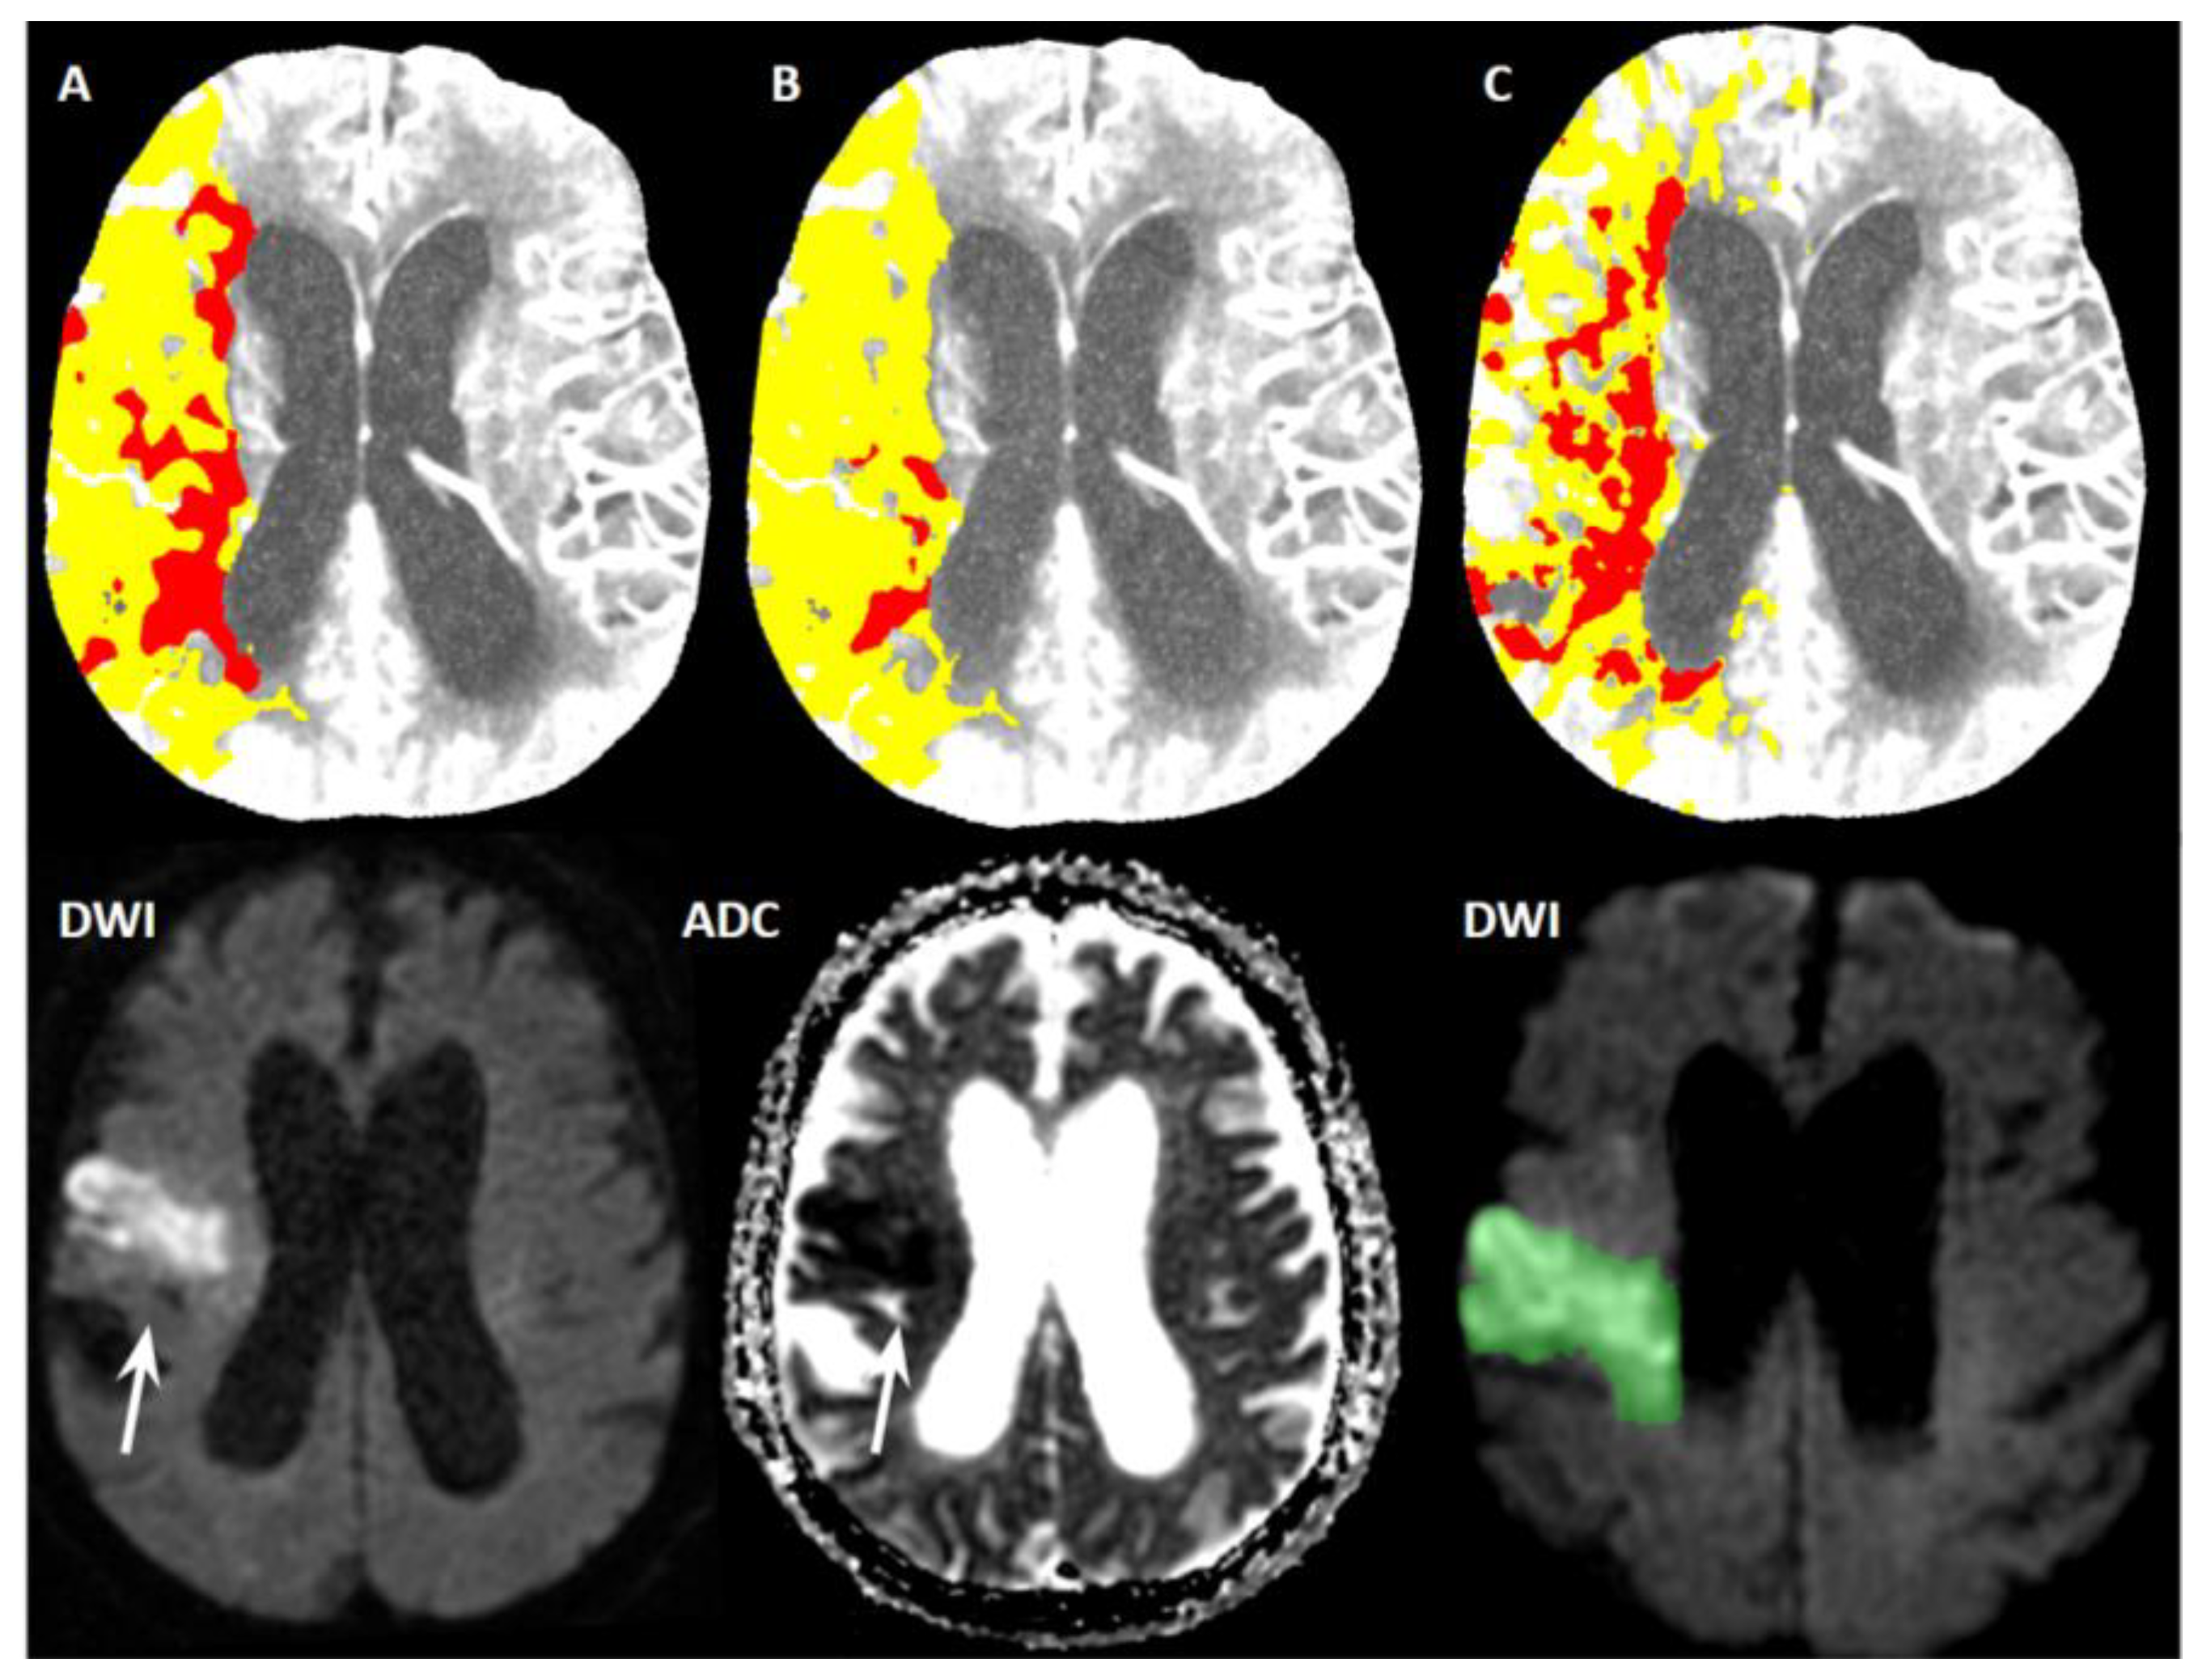

- Setting A (our adjustment of default syngo.via settings)

- Setting B (adjustment of syngo.via settings by Siemens professionals)

- Setting C (default syngo.via settings)

- Setting A (CBF < 30%, TMAX > 6 s): The median ischemic core volume was 34 mL (IQR 46.5 mL).

- Setting B (CBF < 20%, TMAX > 6 s): The median ischemic core volume was 10 mL (IQR 24 mL).

- Setting C (CBV < 1.2 mL/100 mL, CBF < 27 mL/100 mL/min): The median ischemic core volume was 23 mL (IQR 22 mL).